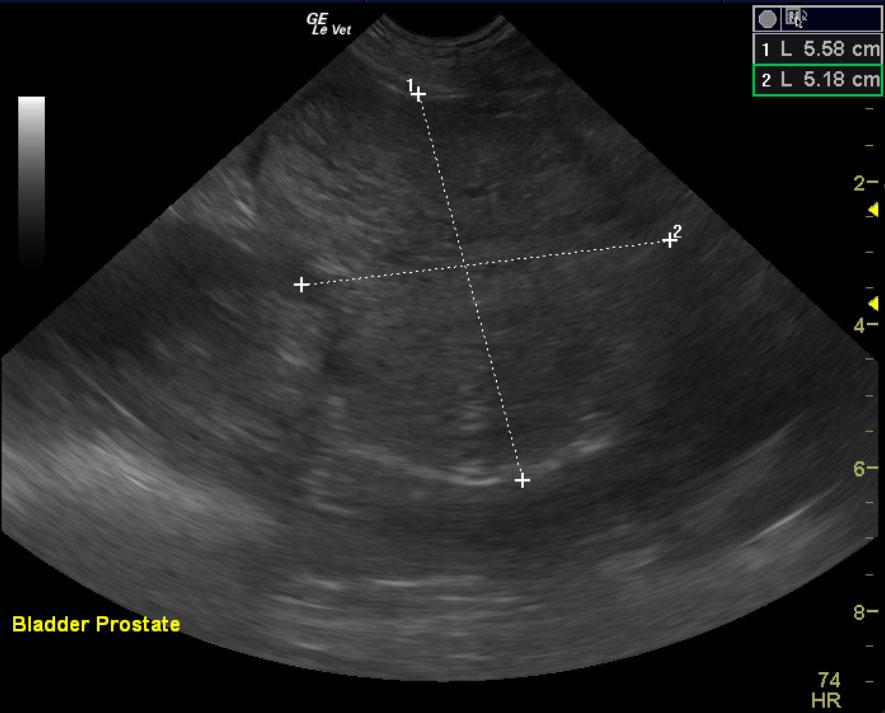

A ten year old intact male labrador retriever was presented with an enlarged prostate and painful rear end. Serum biochemistry and CBC were within normal limits. The urine specific gravity was 1.022 with mild pyuria.